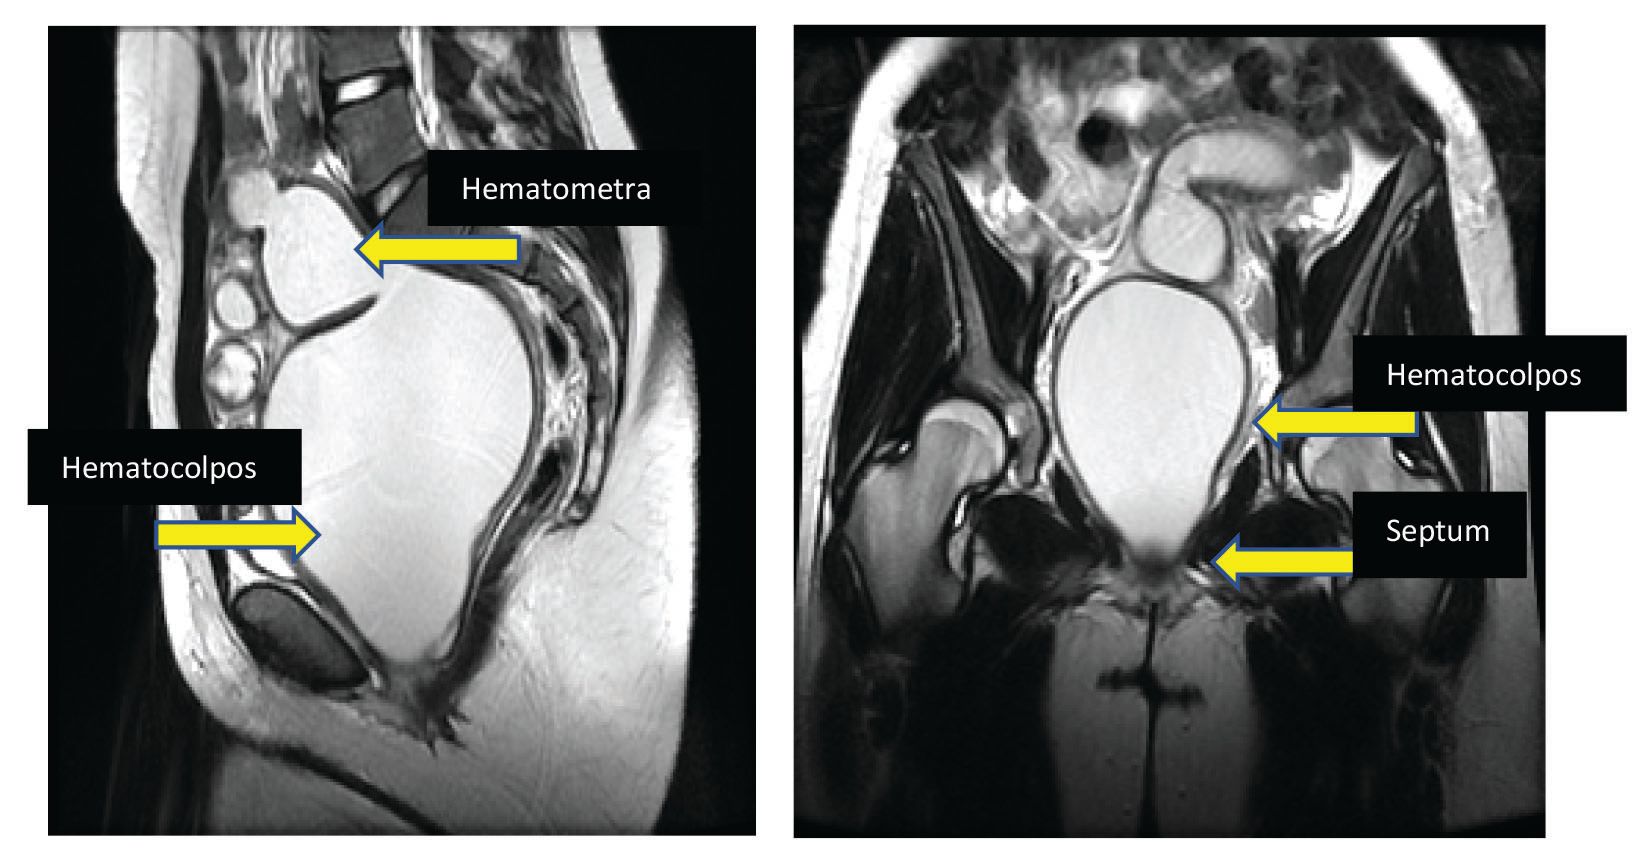

A 13-year-old girl presents with significant cyclical abdominal pain and amenorrhea. She has Tanner stage V breasts and genitalia. Her external genital exam is completely normal with an appropriate hymenal opening. There is no bulge on the perineum. A small cotton swab placed through the hymen stops at 4 cm. On rectal exam you feel a bulge anteriorly, approximately 4 cm into the rectal canal. Ultrasound reveals a large blood-filled cavity, so you obtain an MRI (Figure 5). What is your diagnosis?

Figure 5. MRI of a 13-year-old girl with transverse vaginal septum. Credit: Collection of Monica Woll Rosen, MD, University of Michigan

This scenario is most consistent with a transverse vaginal septum. The septum can be located at different levels of the vagina, but external genitalia appear normal. Septa can vary in thickness, with whole segments of the vagina undeveloped.

Because cases of transverse septa are rare and difficult to repair, they should be managed at tertiary centers by experienced pediatric and adolescent gynecologists or other gynecological surgeons.

Surgery is usually performed vaginally, with assistance abdominally or laparoscopically. Surgery involves resection of the septum, which relieves the obstruction, followed by either a simple pull-through vaginoplasty or by using a skin or buccal graft to cover the defect.15

It is imperative that patients perform patient-led vaginal dilation after surgery. A recent study showed that of 21 patients who underwent transverse septum resections and had a postoperative complication of vaginal stenosis or scarring, 14 (56%) either did not dilate afterward or did not dilate correctly.14 Therefore, when a transverse septum is diagnosed, menstrual suppression is usually initiated until a patient is old enough to dilate on her own.